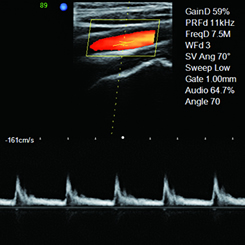

• 外周血管